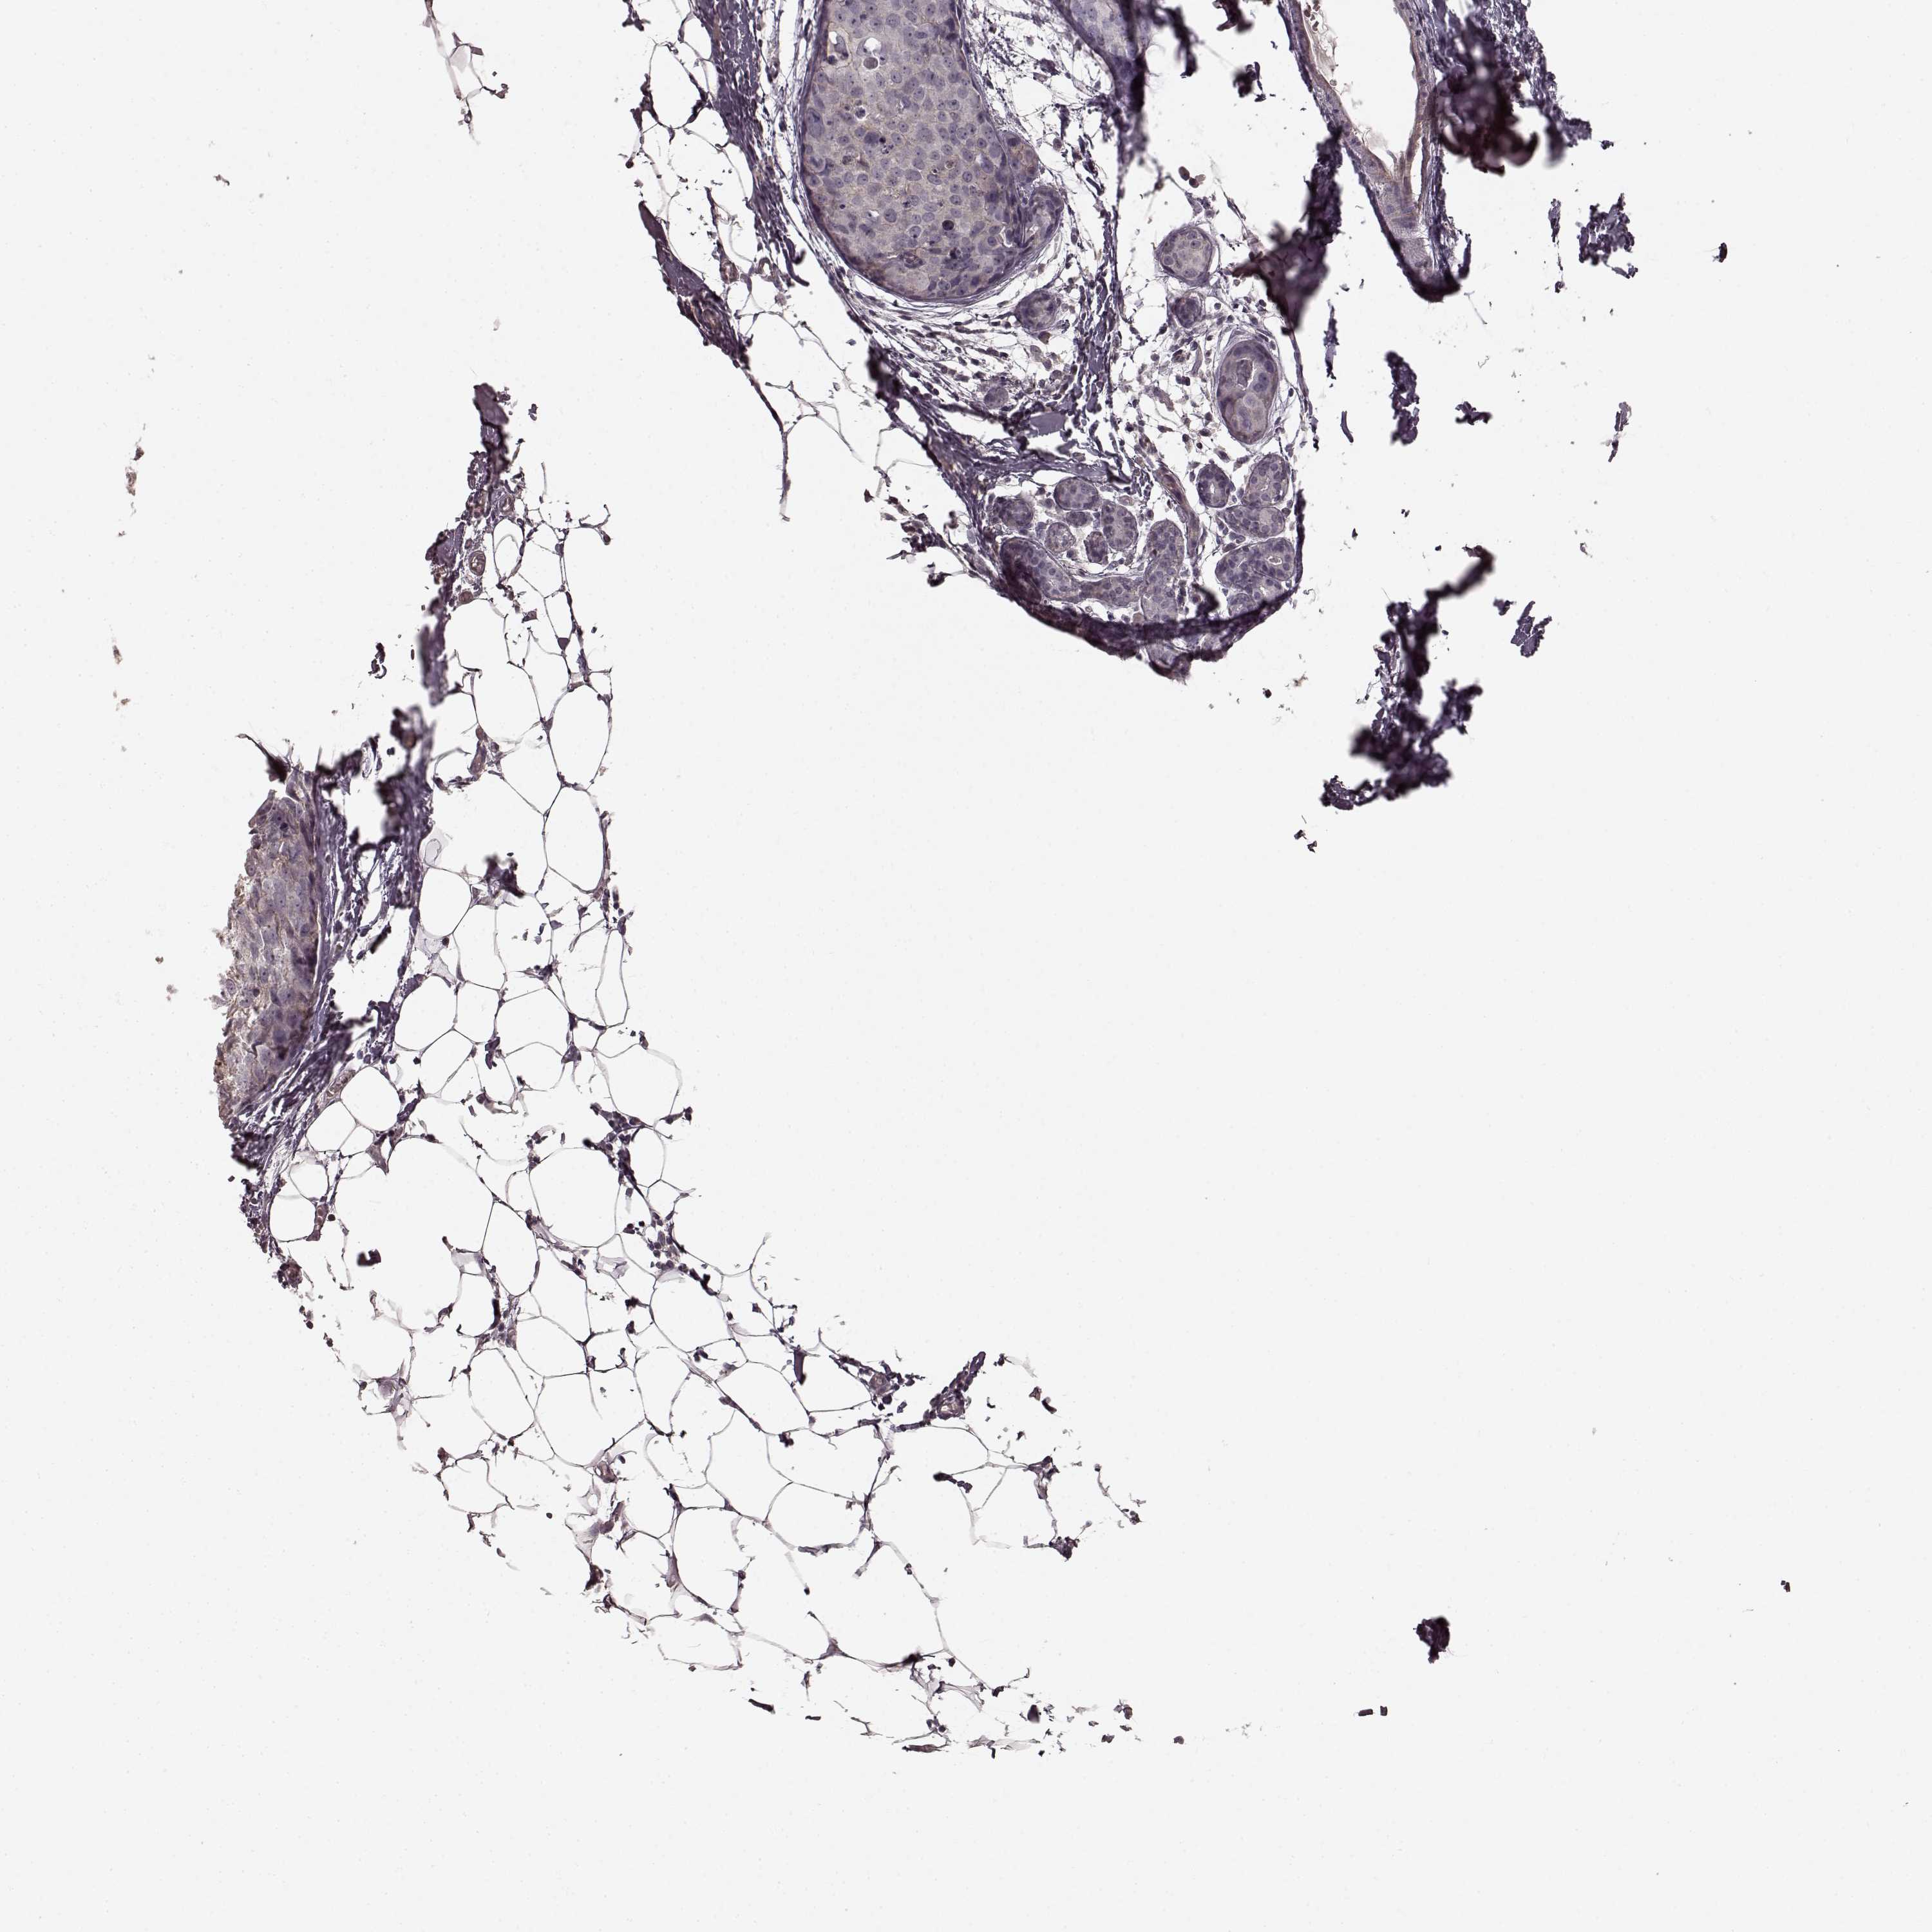

CANCER BREAST CANCER Show tissue menu

BRCA TCGA BRCA VALIDATION PROTEIN EXPRESSION

ANTIBODIES

AND

VALIDATION